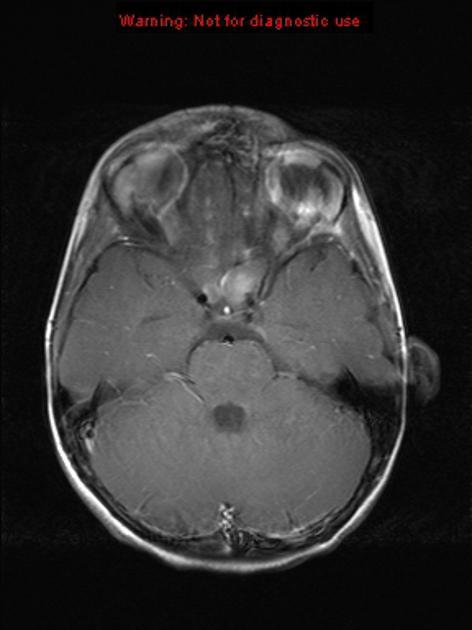

案例六

基本病史:2 岁男孩,近期发现左眼突出。

图 6 MRI 检查轴位 T2WI,T1WI 和矢状位 T1WI 增强序列显示,左侧视神经肌锥内段见类圆形稍长 T1 长 T2 明显异常信号,呈明显强化